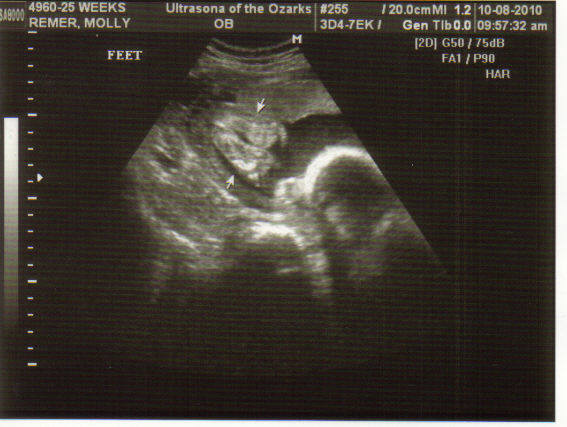

Here are two cute pix of her little feet. The blob nearby is her HEAD, because she is all squished up with her feet by her head.